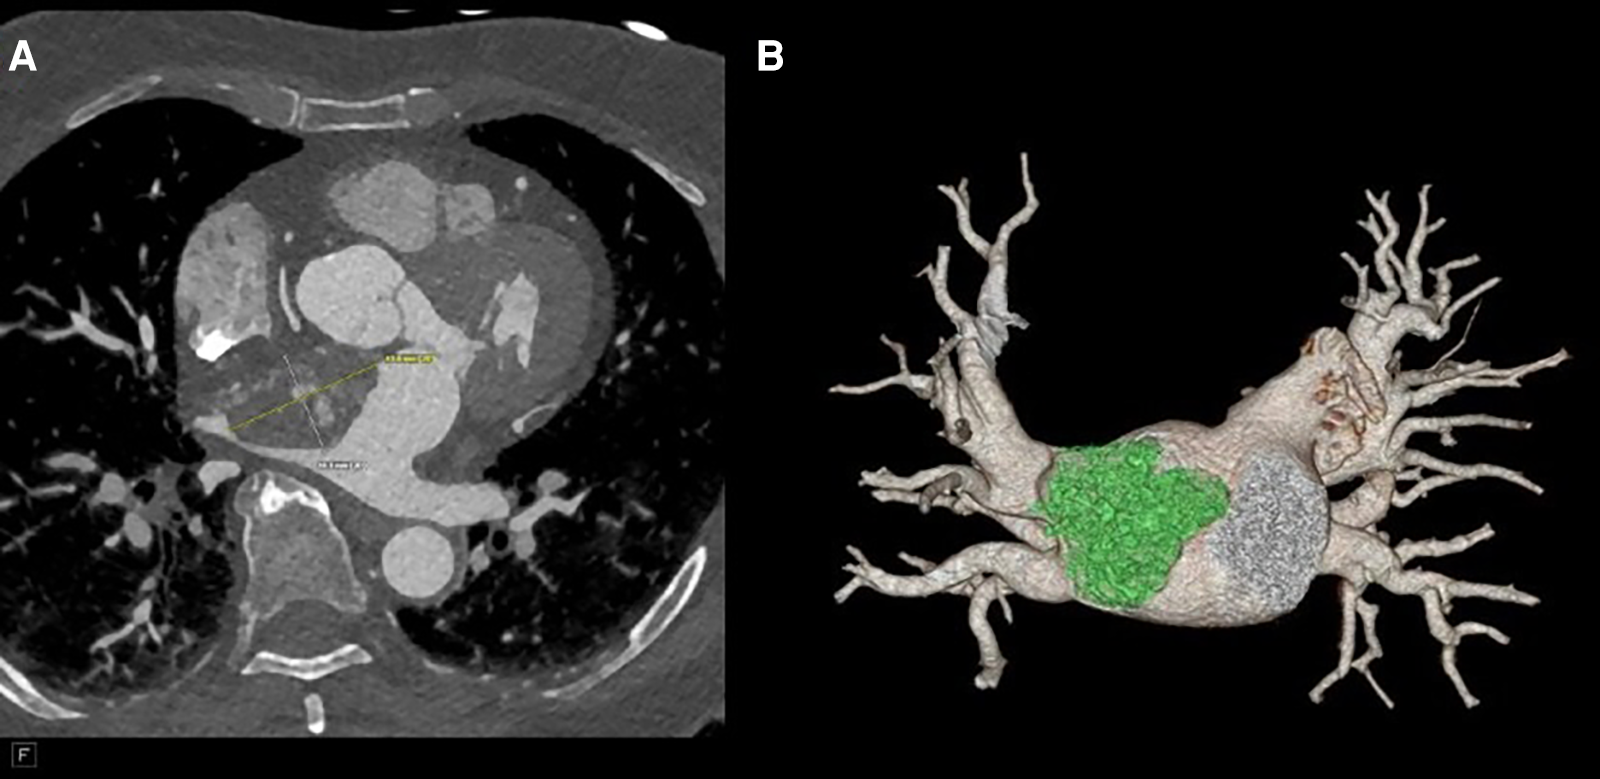

Figure 2

(A) CTA revealing a 41 mm × 27 mm × 33 mm broad-based lobulated mass in the left atrium that extends into the mitral annulus. (B) CTA reconstruction to show the mass extending to the right upper pulmonary vein (RUPV).

Her physical examination was unremarkable, as exemplified by the fact that her heart sounds were normal. A brain magnetic resonance imaging (MRI) did not show signs of ischemia or prior infarction. An echocardiogram in the ED demonstrated a left atrial mass with a broad base attachment to the atrial septum (Figure 1) that extended from the opening of the pulmonary veins to the mitral annulus. Subsequent investigation with coronary computed tomography angiography (CCTA) revealed a 41 mm × 27 mm × 33 mm broad-based lobulated mass in the left atrium that extended onto the mitral annulus (Figure 2). The mass was isointense on T1-weighted images and hyperintense on T2-weighted images and showed restricted diffusion (Supplementary Figure S1). There was heterogeneous enhancement on both early and late postcontrast images. The findings were compatible with a cardiac myxoma (Supplementary Video S1).

Following the reported imaging findings, a careful surgical plan was discussed with the multidisciplinary team for resection of the mass. A CCTA with a three-dimensional (3D) reconstruction of the mass, including a 3D-printed model of the patient's heart depicting the mass and relationship with adjacent structures, was obtained to help with surgical planning (Figure 3). The 3D CT model redemonstrated a polypoid, heterogeneously enhancing left atrial mass attached to the entire left side of the atrial septum and measuring approximately 44 mm × 28 mm × 40 mm. The appearance on the CCTA and the location were consistent with a cardiac myxoma. The mass occluded the right superior pulmonary vein ostium during the atrial systole phase. A large-caliber sinoatrial artery branch arising from the proximal segment appeared to be the primary vascular supply to the mass. A transesophageal echocardiogram (TEE) was obtained, which confirmed that the mass was not adherent to the right superior pulmonary vein (Supplementary Videos S2, S3). Therefore, the patient was deemed to be a surgical candidate for a minimally invasive robotic approach given the location of the mass and the lack of adherence to the wall of the right superior pulmonary vein.

Myxomas are often initially diagnosed by echocardiography. The classic presentation is a mobile mass on a stalk arising from the atrial septum. In our patient, a TEE was done prior to surgery to assess hemodynamic function. A cavitated sessile mass arising from the atrial septum was seen. The mass did not have a stalk and exhibited contrast within the body of the tumor. The lack of a stalk from which the tumor arose and its cavitated appearance were atypical for a myxoma, warranting further investigation and planning prior to resection. The mass also extended upward into the right pulmonary veins, which is extremely uncommon. Cardiac MRI (CMRI) often complements echocardiography and offers improved tissue characterization, with cardiac myxomas typically demonstrating hypointensity on T1 images, hyperintensity on T2 images, and little to no perfusion or late enhancement (5). T1- and T2-weighted double-recovery sequences aid tissue characterization. Furthermore, cine cardiac imaging holds great importance in evaluating atrial myxomas because of their high mobility and their tendency to prolapse through the atrioventricular valve during diastole (6). Contrast-enhanced sequences are crucial in distinguishing myxomas from thrombus, as myxomas typically exhibit minimal or nil enhancement during first-pass perfusion, yet display a more heterogeneous enhancement pattern on late gadolinium enhancement (LGE) imaging (7). In our case, the patient's cardiac MRI scan did show findings consistent with those of a myxoma, but it revealed more enhancement than is typical. Cardiac MRI has shown remarkable accuracy in identifying cardiac masses and effectively differentiating between benign and malignant tumors. However, relying solely on MRI has been associated with occasional instances of inaccurate diagnosis. Therefore, adopting a multimodal imaging approach comprising echocardiography, MRI, CT, and possibly positron emission tomography (PET) imaging offers an optimal approach for a comprehensive evaluation and stratification of cardiac masses (8). Given the atypical characteristics and location of our patient's left atrial mass, a CT angiogram with a 3D reconstruction of the heart depicting the mass was requested to guide the diagnosis and surgical planning. The mass was heterogeneously enhancing and polypoid in shape. The mass did not infiltrate or invade surrounding structures. This observation holds considerable significance as it reduces the likelihood of the tumor being a malignant one (9). However, it did extend to the ostium of the right superior pulmonary vein, occluding it during atrial systole. It is hard to ascertain whether the mass was the source of our patient's symptoms, but these findings could potentially explain the patient's orthostatic syncope and dizziness. A case report in the literature describes a patient presenting with syncope and dyspnea, who was found to have a left atrial myxoma extending into and occluding the left pulmonary veins and causing pulmonary infarction (10). However, in our patient, the mass did not extend or occlude the mitral valve, which made it feasible to adopt a robotic approach. Furthermore, the mass received blood supply from the small sinoatrial node branch of the right coronary artery. This was visualized precisely and with high spatial resolution on the 3D-printed model, which also showed the extent of expansion of the mass into the right upper pulmonary veins (Figure 4). The printed model also provided for visualization of the best approach to enter the left atrium without disruption of the mass. A possible implication of this occurrence is the formation of a fistula between the sinoatrial nodal artery and the right atrium after surgical resection of the atrial myxoma. For this reason, special attention should be paid to ligating neovascularized branches feeding myxomas during the surgical procedure (11).